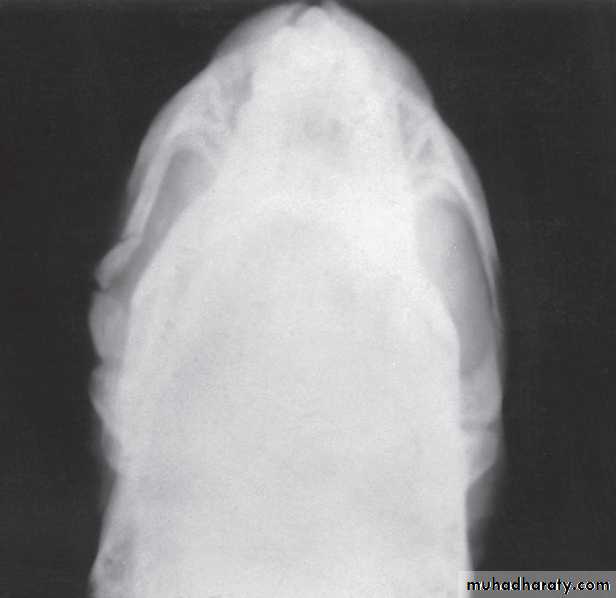

Submentovertex View